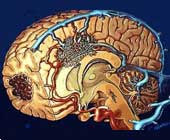

額葉症狀群(垂體卒中)(二)垂體卒中(pituitary apoplexy) 垂體卒中時體積增大,鞍內壓力增大,壓迫額葉底部,出現視神經、視交叉的麻痹,亦可出現Ⅲ、Ⅳ、Ⅵ顱神經麻痹。當壓迫丘腦下部時,則出現意識障礙。